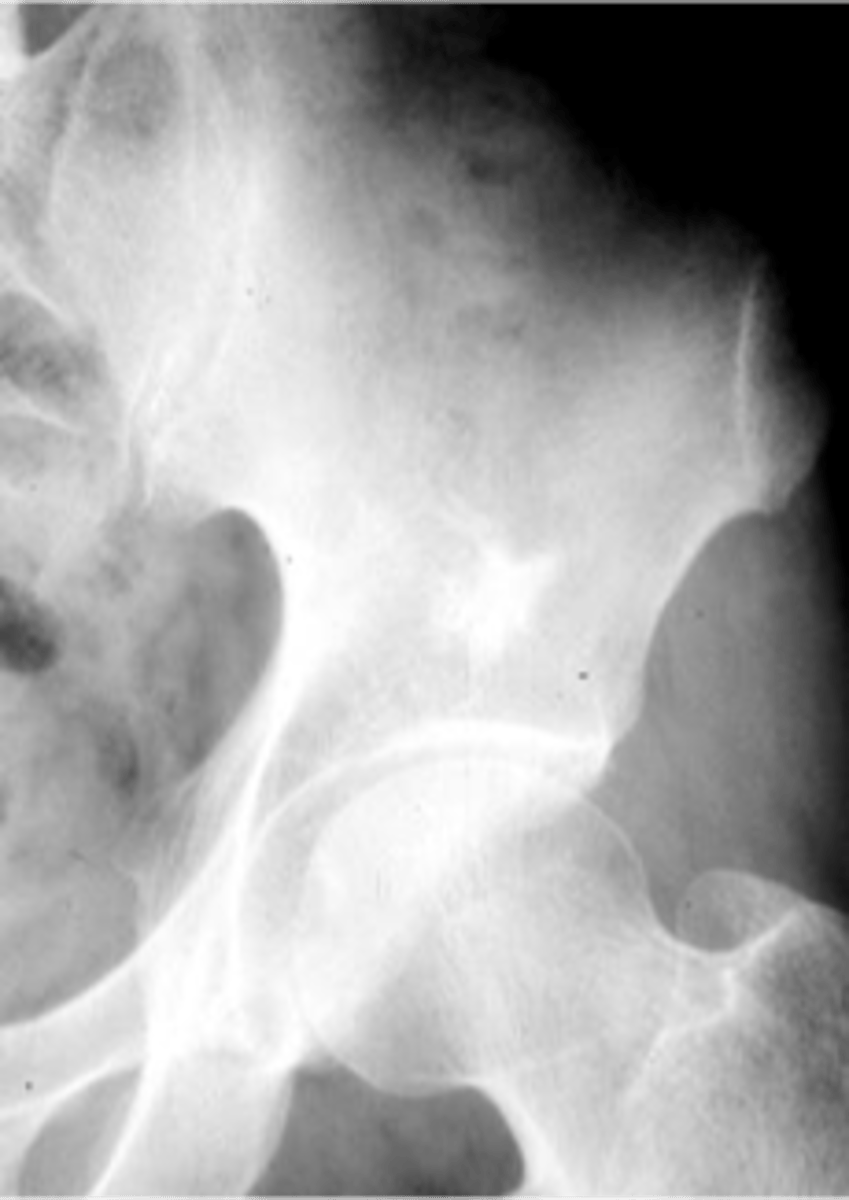

58

New cards

Geographic bone blister

ID radiographic feature of non-ossifying fibroma indicated by top arrow

<p>ID radiographic feature of non-ossifying fibroma indicated by top arrow</p>

59

Septations

ID radiographic feature of non-ossifying fibroma indicated by bottom arrow

<p>ID radiographic feature of non-ossifying fibroma indicated by bottom arrow</p>

60

Pathologic fracture

Non-ossifying fibroma with _____

<p>Non-ossifying fibroma with _____</p>

61